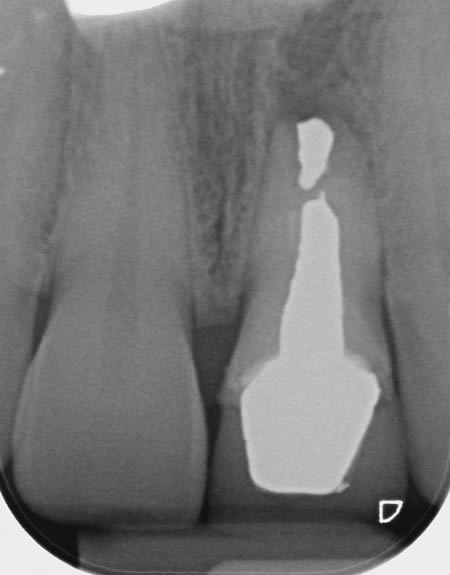

Case F

Before Treatment

This gentleman came to see me after his crown decorated. He was fed up with being called a pirate by his grandchildren and decided to do something about the gap.

Due to an absence of infection and an atraumatic extraction, the removal of the tooth was followed by immediate implant placement. The implant was restored with an Atlantis abutment and bonded crown.